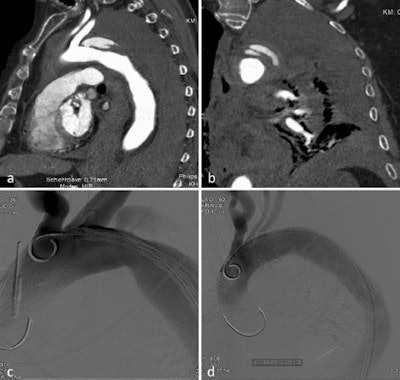

Also, 3D vascular reconstruction with vascular segmentation and centerline reconstructions are often helpful in aortic measurements for stent graft planning, which is easier to perform in the arterial phase than in the venous phase.

Ruptured aortic aneurysm: The diagnosis of which depends on measurement of the vascular diameter.

Iatrogenic aortic injury: May be caused by direct external injury from surgical procedures or an endovascular approach.